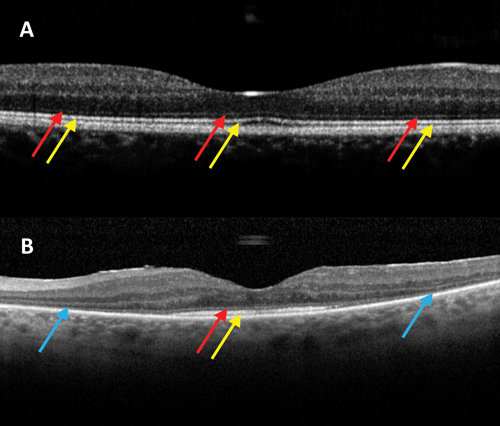

Figure 4: OCT image centred on the macula taken from a patient with x-linked retinoschisis. A: spokewheel-like maculopathy. B: typical macular schisis as seen at the level of the green line observed in A.

Boys typically present in the first or second decade of life with strabismus, amblyopia, anisometropia, or having failed school vision screening [32,38]. The characteristic fundus abnormality is a cystic spokewheel-like maculopathy (foveal schisis), present in about two-thirds of males, and most readily observed with SD-OCT (Figure 4). Fifty percent of affected males show additional peripheral retinal changes - often a (usually lower temporal) peripheral retinoschisis [19]. Other peripheral retinal changes include pigmentary retinopathy, perivascular sheathing and capillary closure. Retinal detachment and vitreous haemorrhage may complicate X-linked retinoschisis [32].